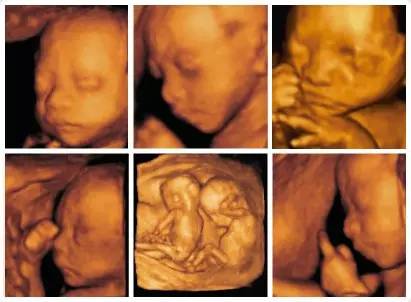

超声影像(四维彩超)| 胎宝宝在子宫里会感到孤独吗?

想知道宝宝在肚子里干什么吗?那就来无锡百佳妇产医院做一次四维吧!超声影像(四维彩超)能清晰的看到宝宝的一举一动,让你提前和宝宝见面,除此之外,超声影像(四维彩超)也是孕期检查最重要的一环,其中孕22~26周是最佳检查时间噢~